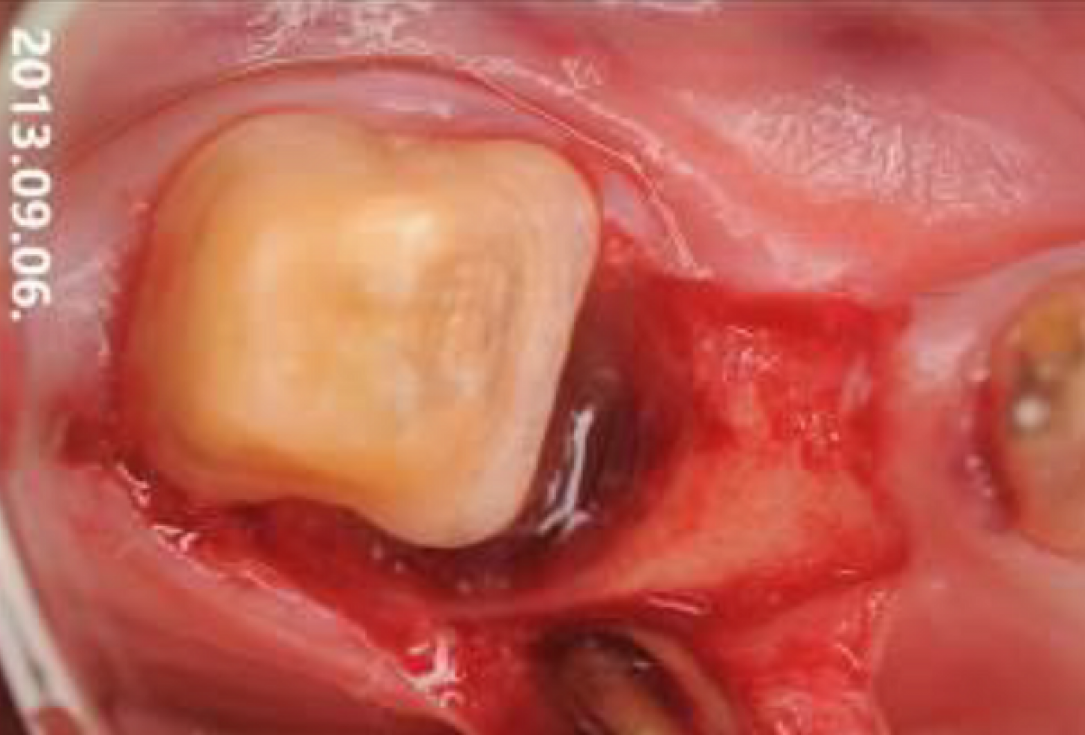

02/06 - Intra-operative view. Cleaned intrabony defect.Intrabony defect treated using Straumann® Emdogain®, cerabone® and Jason® membrane - Dr. D. B. Hangyási